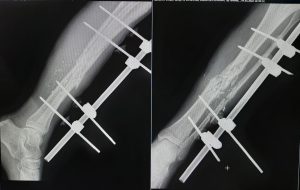

From the first days we started to provide assistance to wounded civilians and the military from different parts of our country. Our work is to diagnose various injuries of the chest, abdomen, skull, pelvis and especially the limbs. We help thoracic, abdominal and facial surgeons, ophthalmologists, and especially orthopaedists in preoperative and postoperative stages of the treatment.

One of our tasks, as radiologists, has been to find foreign bodies in the people’s arms, legs, abdomen and thoracic wall with help of radiography or ultrasound. We also help in finding traumatic injuries to internal organs. Despite of lack of a new equipment we try to help all our patients as much as it possible. Psychological support of patients is also important in our work which I am are doing.

The X-ray in the Figures in this article are of one of our civilian patients who has recently lost one of his hands, one leg and damaged other leg after the Russians came to his village in the south of Ukraine.